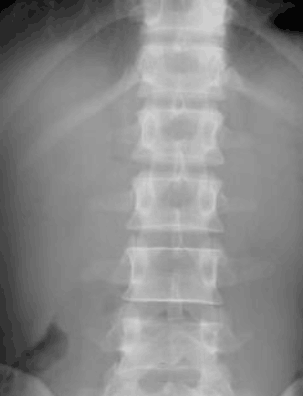

强直性脊柱炎可以引起骨骼过度生长,导致骨骼异常连接,被称为“ ...

强直性脊柱炎疾病全身表现轻微,少数重症者有发热、疲倦、消瘦、 ...